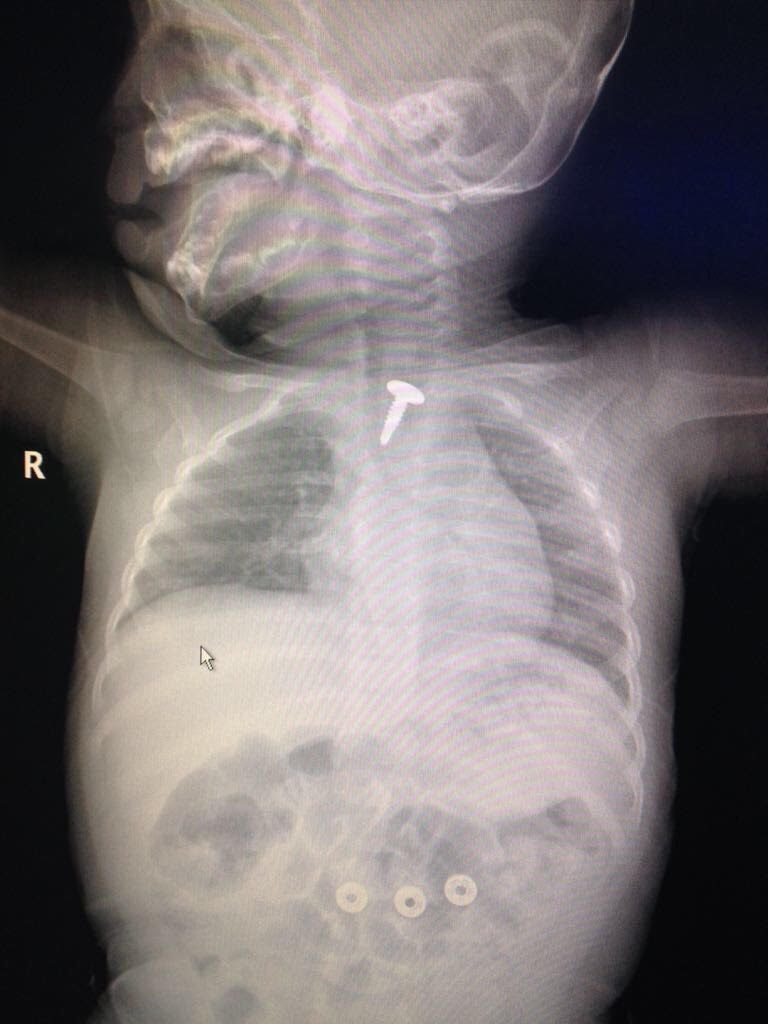

تمكّن فريق طبي في مستشفى الملك خالد بتبوك من إنقاذ حياة طفل يبلغ من العمر 6 أشهر ابتلع مسماراً أدى إلى انسداد مجرى التنفس لديه، وكاد يودي بحياته.

وكان الطفل قد حضر إلى قسم الطوارئ برفقة ذويه، وبإجراء الفحوصات الفورية والأشعة تبين وجود مسمار طوله 1.5 سنتيمتر داخل الجهاز التنفسي.

وعلى الفور تم إدخال الطفل غرفة العمليات، حيث أُجريت له عملية بالمنظار وتم استخراج المسمار، ويتمتع الطفل حالياً بصحة جيدة ولله الحمد.